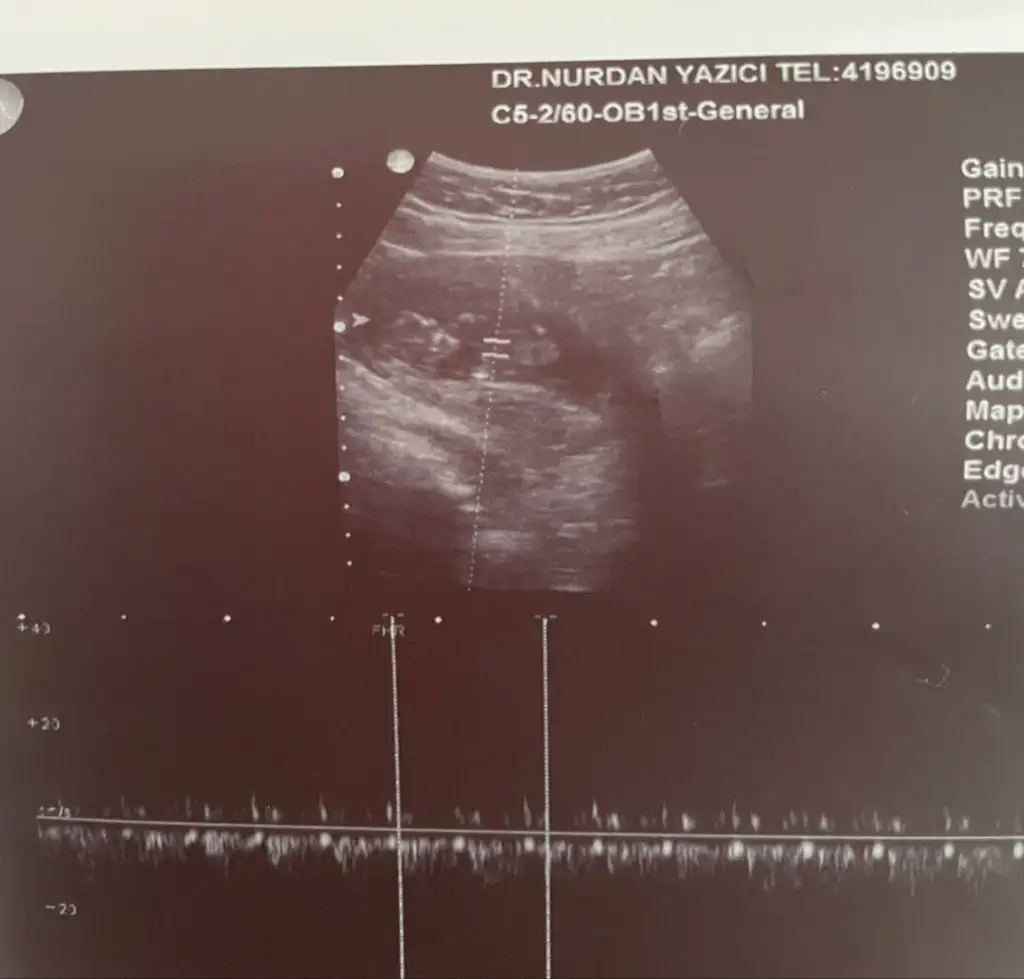

Bu ultrason da görünüyor mu nubUltroson fotoğrafından pek belli olmuyor sizin genelde nub teorisi doğru çıkıyor nub gözükmüyor sizinkinde

Bunda belli mi nubu sizce nedirUltroson fotoğrafından pek belli olmuyor sizin genelde nub teorisi doğru çıkıyor nub gözükmüyor sizinkinde

Erkek bence nubu çok görünmüyor ama tahminimBunda belli mi nubu sizce nedir